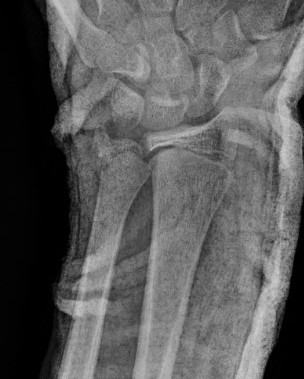

Distal radius buckle fracture

- torus / buckle fractures: compression and unicortical bend / buckle of one cortex with no clear break

Acceptable alignment

Angulation (all numbers debatable)

- < 8: 25-30°

- > 2 years of growth remaining: 15 - 20°

- < 2 years of growth remaining: < 15°